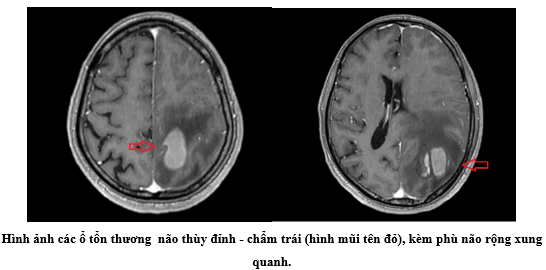

Chỉ trong vòng 5 ngày trước khi nhập viện, cơn đau đầu âm ỉ tăng dần, đi kèm biểu hiện yếu tay và chân phải khiến bệnh nhân phải đến khám. Kết quả chụp cộng hưởng từ (MRI) sọ não cho thấy nhiều tổn thương bất thường ở thùy đỉnh – chẩm trái, kèm phù não diện rộng và hiệu ứng khối, đẩy lệch đường giữa.

Đây là dấu hiệu điển hình của tổn thương choán chỗ trong não – một tình trạng nguy hiểm, thường gợi ý đến u não hoặc di căn từ nơi khác.